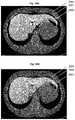

FIG. 28A illustrates three representative slices of the spleen with “double windowing”.

FIG. 28B illustrates three representative slices of the liver with “double windowing”.